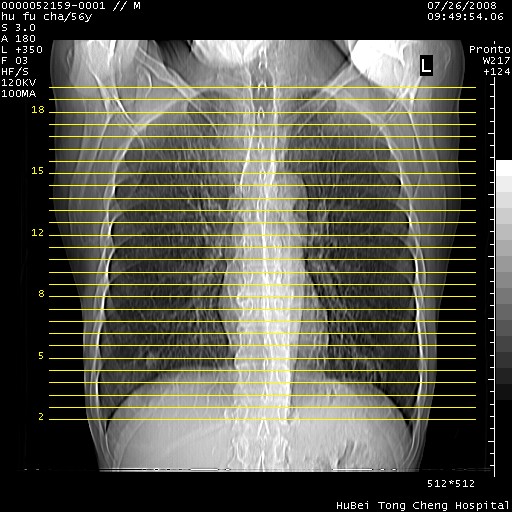

以下是引用zsl6918在2008-8-25 22:47:00的发言:[br]胸骨,胸椎及肋骨均可见多发转移表现,肝内低密度结节不除外转移。原发灶可能在右肺。双侧可见支扩表现。